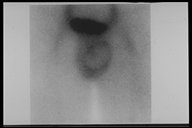

Testicular scan is the best investigation to confirm the testicular torsion, No uptake of radionuclide at the testicular core but increased uptake around the testis

" Halo sign " with increased uptake of radionuclide around the testis but no uptake at the core suggests that the vascular supply is interrupted in a case with right testicular torsion